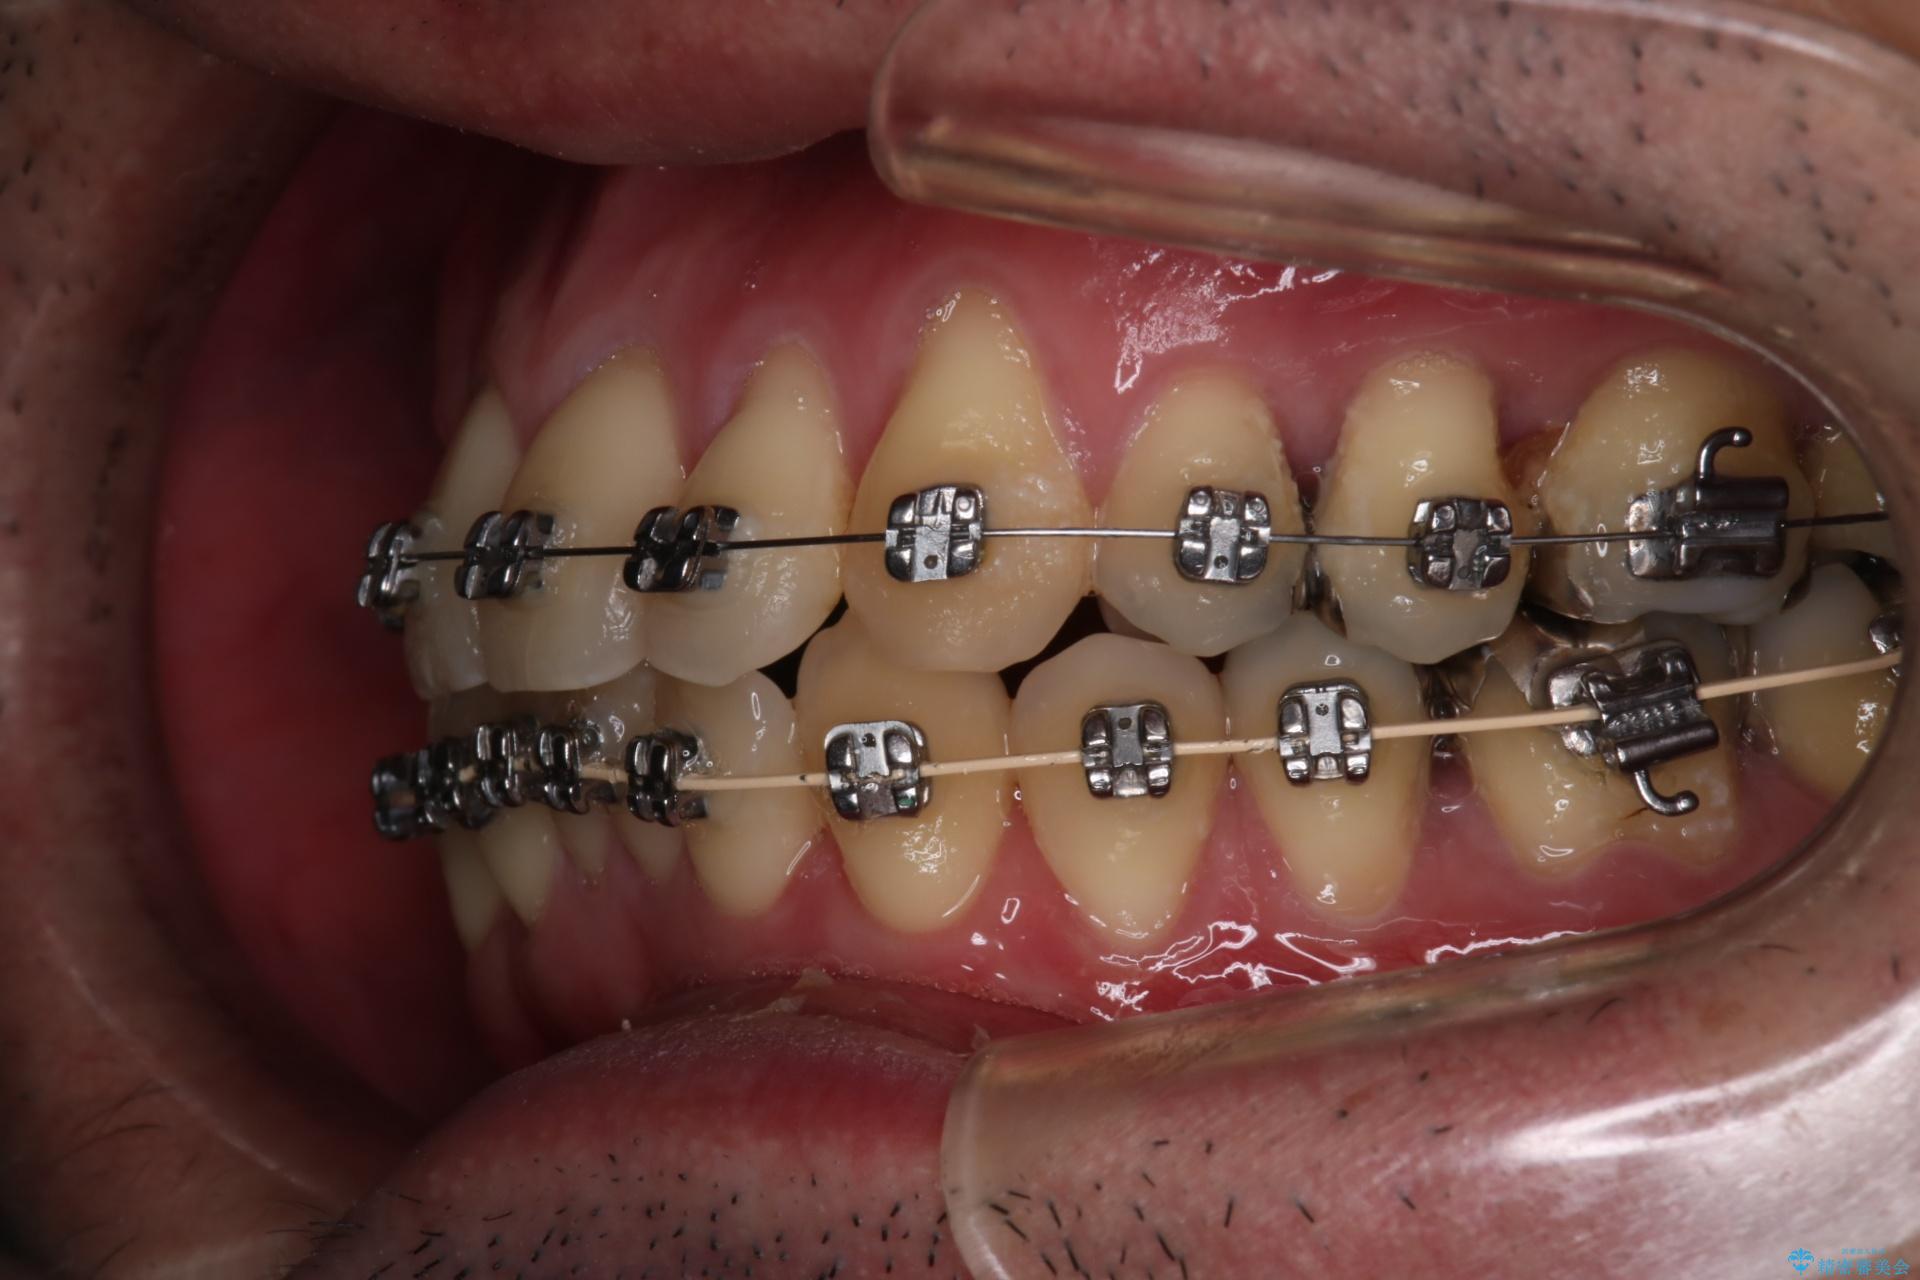

【メタル装置】1本のみ抜歯してワイヤー矯正

- 矯正装置

- メタル装置

- 右上2番目の歯が舌側転位していることと前歯の叢生(がたつき)を主訴に来院されました。

右上の犬歯が初診時よりかなり歯根露出しており、矯正の力をかけるとさらに歯根露出するリスクがあるため、右上の2番目の歯を前に出すためにも

右上の犬歯を抜歯して歯並びを整える治療計画を立てました。

下のがたつきをとるために、IPR(歯と歯の間を削る処置)も行って歯を並べていきます。